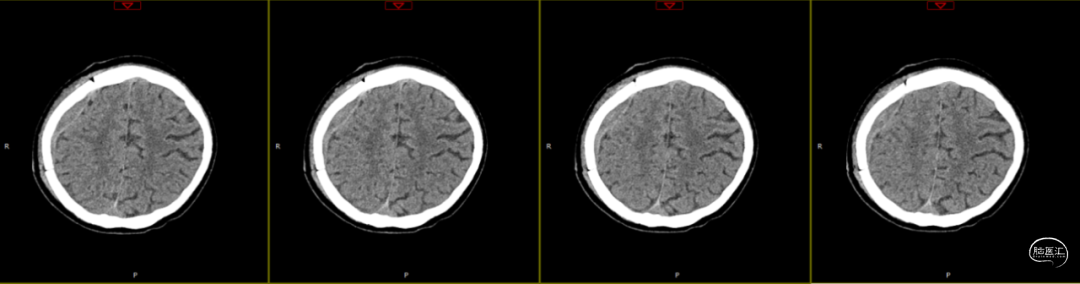

查体:嗜睡-昏睡状态,精神差,刺激睁眼,简单应答,肢体活动简单从嘱。GCS13分。双侧瞳孔等大等圆,直径2.5mm,对光反射灵敏,伸舌欠合作。转头、耸肩欠合作,四肢肌力4级,肌张力正常,颈抵抗(+),双Babinski sign未引出。枕部可见约5*4cm皮下血肿,压痛,拒按。周身多发片状皮肤擦伤。颅脑CT:双侧额叶脑挫裂伤;右侧顶颞枕部硬膜外、硬膜下血肿;蛛网膜下腔出血;右侧颞骨骨折累及右侧人字缝、顶乳缝,右侧顶乳缝旁小骨片;头皮软组织损伤、局部皮下血肿;双肺挫伤可能。

因患者在病情观察期间意识状态变差,昏睡-浅昏迷状态,予以急症手术治疗,清除硬膜外血肿,鉴于术中脑组织压力不高,予以骨瓣回置,术后严格控制血糖水平,常规使用抗生素(头孢唑林钠)预防感染。

术后第1天颅脑CT复查(如上图)